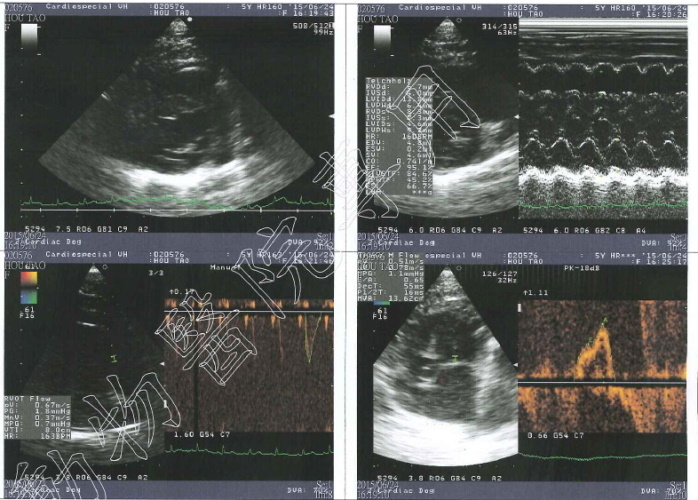

2015/4月厚道食慾胃口下降,就醫檢查發現肝指數較高,超音波無明顯異狀,X光片肺部較多白影處,可能上呼吸道感染,或者是剛救援時感染肺炎的後遺症,給予口服抗生素,因為厚道的牙齒所剩無幾,又口炎需要噴口樂減緩不舒服,因為肝指數偏高每天需要打皮下點滴75CC補充水分,治療後食慾慢慢恢復,五月追蹤肺部狀況進行X檢查,發現心臟旁稍有異樣,建議要轉院進行心臟超音波檢查,約診心臟專科專心動物醫院進行詳細檢查,檢查結果稍微心室肥厚,可能先天就這樣,也不一定會惡化,需半年回診監控情況,最久一年一定要回診掃心超,目前不需吃藥,持續每天打75ml,專心掃描心臟超音波的費用還請各位幫忙。